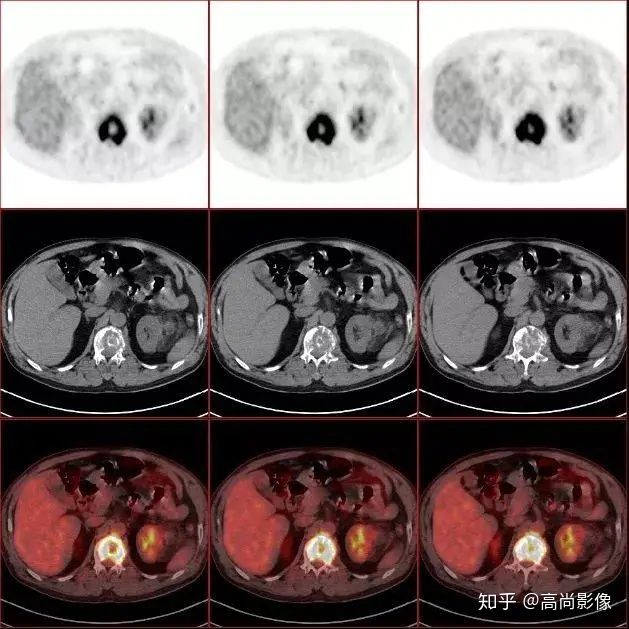

與方大爺有類似病情的一位患者,化療前后的PET/CT影像顯示,腫瘤得到了很好的控制。

肺癌化療前評估的MIP圖

(最大密度投影圖)

肺癌化療后評估的MIP圖

由此可見,惡性腫瘤化療前后的全身PET/CT評估有多重要,尤其對于惡性腫瘤患者來說,時間就是生命,早一天完善診斷,早一天得到正確的治療,預(yù)后就會更佳。